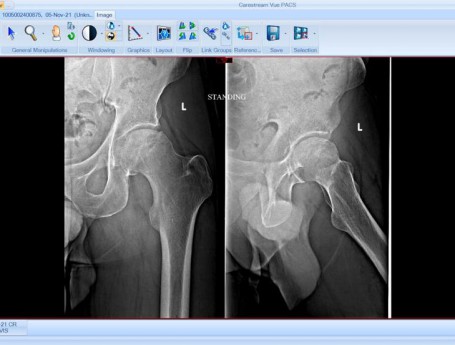

Total Hip Arthroplasty Anterior Approach